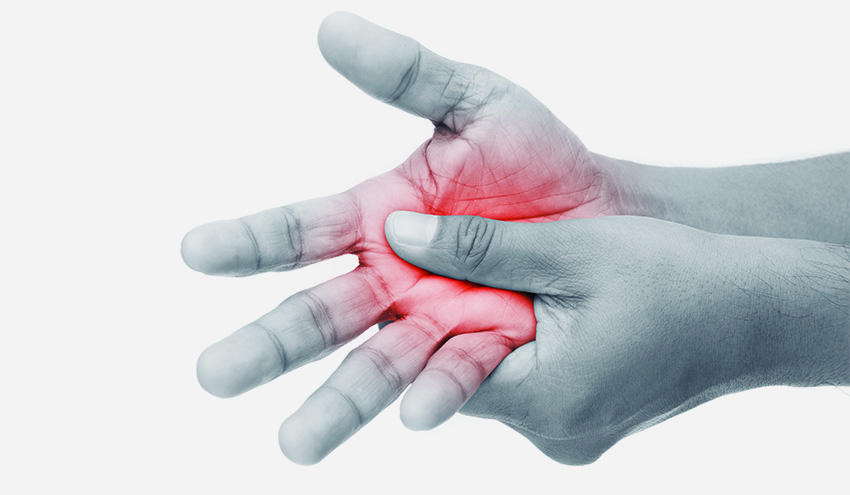

L’artrite psoriasica è una malattia infiammatoria cronica che riduce la mobilità e l’agilità dei pazienti, caratterizzata da dolore, gonfiore e rigidità delle articolazioni interessate, e che porta ad aumentato rischio di sviluppare il diabete di tipo II, compromettendo decisamente la qualità di vita dei pazienti e lo svolgimento delle normali attività connesse alla vita quotidiana.

Lo studio presenta un nuovo modello animale, unico nel suo genere, che ricapitola tutti gli aspetti dell’artrite psoriasica contemporaneamente (eritema, desquamazione ed ispessimento della pelle, degenerazione delle vertebre, ispessimento sinoviale e perdita di cartilagine articolare nel ginocchio), ottenuto attraverso modifiche genetiche (inserimento del gene “IL-23”, per l’interleuchina 23 proinfiammatoria).

“L’importanza del nuovo modello – dichiara il professor Pola – si concretizza nella possibilità di aprire finalmente un varco nell’approccio terapeutico in particolare della degenerazione discale e dell’artrite della colonna connesse a questa patologia e, quindi, di poter migliorare la qualità di vita dei pazienti”.

I topolini modificati geneticamente hanno sviluppato, già dopo una singola iniezione del gene, la malattia, con tutti i sintomi a partire dalle manifestazioni cutanee fino alle disfunzioni discali e articolari.

Lo sviluppo di questi sintomi fa di questo topo l’unico modello animale di PsA esistente al mondo e il trattamento con anticorpi specifici per l’IL-17 ha dimostrato un miglioramento dei sintomi della patologia, rimarcando l’importanza del lavoro per quanto riguarda lo sviluppo di nuovi approcci terapeutici. “Questo rappresenta un eccellente modello di PsA che ripercorre tutti i sintomi della patologia dell’uomo”, spiegano gli autori. “Il modello può finalmente essere usato per testare le terapie per aiutare i nostri pazienti”, continuano.